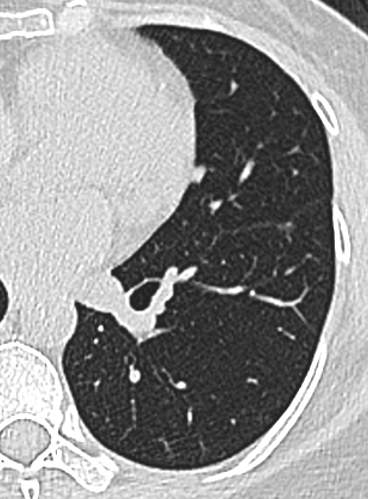

21年底左下肺,直径5.2mm:

img